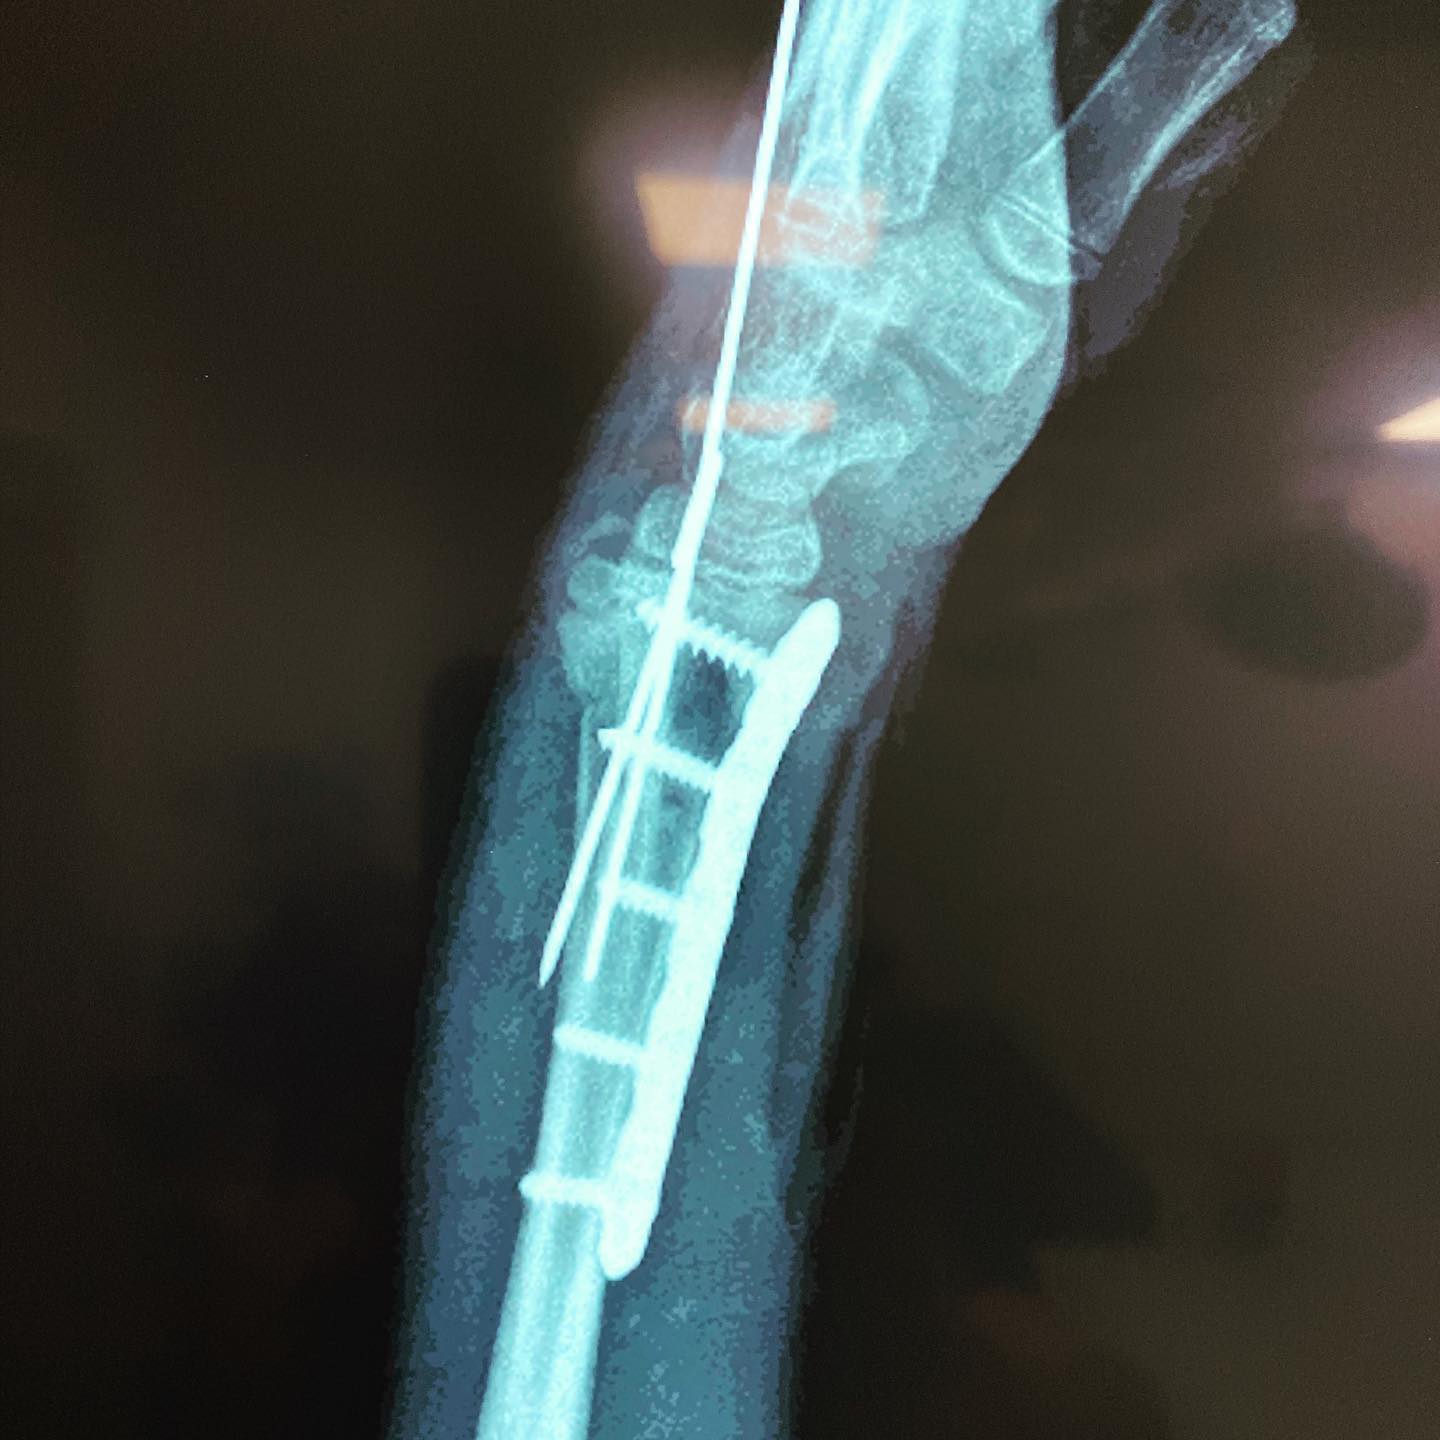

fractura de antebrazo

Cité a Josué para seguimiento y como ya está recuperado al 💯 de la cirugía por fractura de su antebrazo, le di el alta. En su visita me regaló una deliciosa sandía.🍉